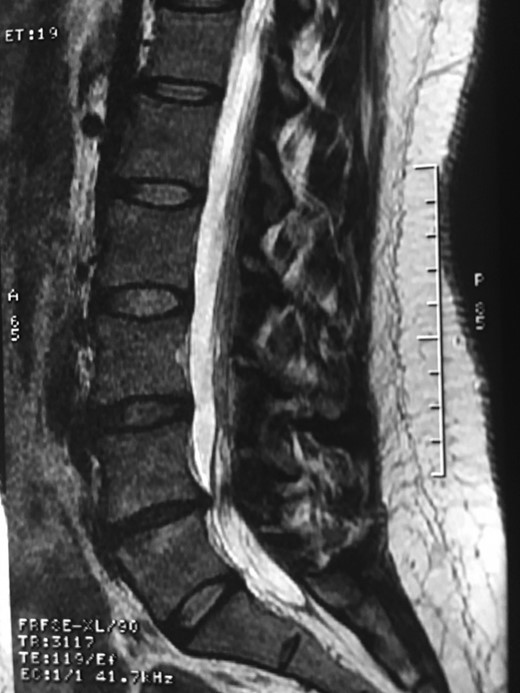

A 42-year-old female presented to the clinic with a history of chronic low back pain. She reported no relevant medical history. She had already been treated in the last 4 years by general practitioners with analgesics and home based physiotherapy with no satisfactory results. She had two previous admissions to the emergency department where morphine was prescribed to control the pain on her lower back. She was under ambulatory treatment with diclofenac, and tizanidine with partial relief of symptoms. Her main complaint was pain on the lower lumbar back with no radiation to the lower extremities. In her physical evaluation she presented limitation to full rotation and bending of the lumbar spine due to pain. Lasegue sign was negative, sensitivity, reflexes, sagittal balance, distal muscular strength and pulses were normal. Radiographs showed an overdeveloped left transverse process of the fifth lumbar vertebra which contacts with the sacrum at the left sacral wing with signs of degeneration at the same site (Fig. 1). Magnetic resonance imaging (MRI) studies were obtained (Figs 2–5). The patient was taken to the operating room where infiltration with 1 mL of lidocaine and 40 mg of Triamcinolone was performed in the pseudoarticulation between the left transverse process and the sacrum under fluoroscopic guidance. She reported a complete relief of pain after the procedure. At three months follow-up she was managed with strengthening and stabilizing exercises for the lumbar spine and postural education was initiated. She remains asymptomatic at her 12 months follow up.

RMN of the patient showing smaller facets in the anomalous articulation and healthy disc compared to the supradjacent one (next figure).

Degenerative changes at the facets and disc in the adjacent segment.

Showing the protective effect of the limitation of the motion in the distal disc to the anomaly.

The partial fusion at the lower part of the lumbosacral transition produces important alterations in normal biomechanics at the levels immediately above and below the LSTV. Changes such as hypermobility and abnormal torque moments are present at the level above the LSTV, predisposing it to early degeneration (early disc pathology and facet joint degenerative disease). Restricted movement below the LSTV produces a protective effect against degeneration of disc and facets and is related to changes (facets are smaller and coronally oriented) in the dimensions of the lower level facet joints [7]. These alterations can be verified in the adjacent levels of the LSTV in our patient.